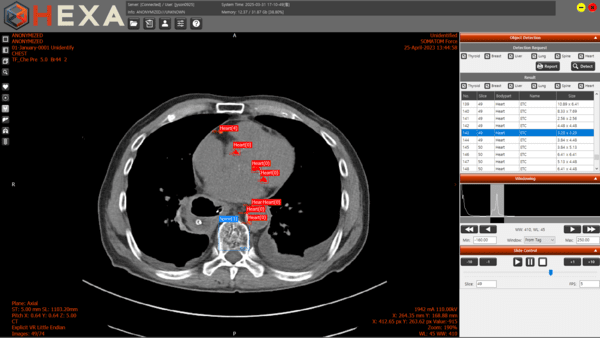

헬스테크 기업 엑스큐브가 흉부 CT 한 번으로 갑상샘·심장·폐·간·유방·척추 등 6개 장기의 이상 의심 부위를 자동 표시하는 AI 진단보조 솔루션 ‘HEXA(헥사)’를 정식 출시했다. 이번 상용화는 엑스큐브가 서울바이오허브의 ‘병원기반 의료데이터 활용 지원사업’에 참여해 실제 임상 데이터를 기반으로 기능을 고도화한 성과다.